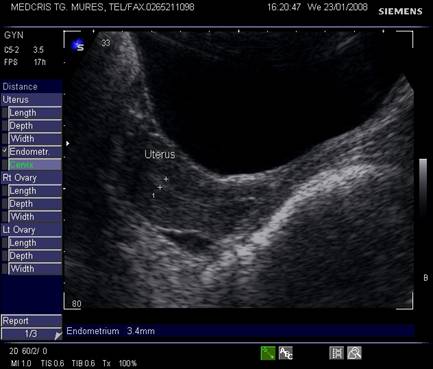

Fig. nr.352. Uter in retroversoflexie , cu hiperplazie de endometru la ecografia abdominala.

Endometrul - grosimea sa este apreciata in sectiune longitudinala. Masurarea se va face de la interfata miometru - endometru la interfata identica, opusa, de pe peretele celalat uterin. Maxim acceptat normal este de 1,5 cm in perioada de premenopauza.[5] Postmenopauza in mod normal nu depaseste 5 mm, de obicei este atrofic si apare ca o imagine ecogena lineara. Daca apare o colectie anecogena postmenopauzala intrauterina, prin atrofie cervicala, aceasta colectie nu trebuie sa fie masurata la calculul grosimii endometriale.[2,6]